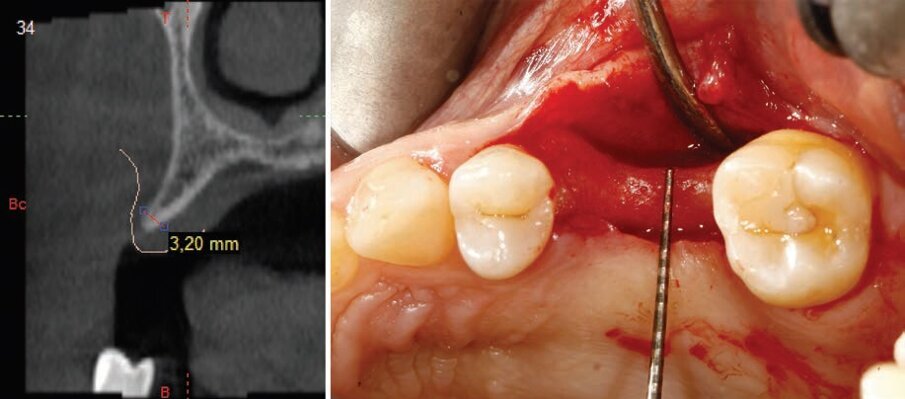

Si presenta all’osservazione una paziente di 64 anni che mostra la mancanza dell’elemento 25 e 26. Clinicamente si può notare un ristretto spazio in senso mesio-distale e un notevole avvallamento vestibolare tipico di una cresta sottile. Diventa quindi necessario un approfondimento radiologico tridimensionale, “cone beam multi FOV” con piccolo volume 4x5 per ridurre la dose radiante. Nella sezione radiologica in prossimità del dente mancante si nota uno spessore osseo di 3.20 mm (Fig. 3) non sufficiente per l’inserimento di un impianto a vite standard. La presenza degli impianti REX PiezoImplant nella libreria implantare del software Implant 3D*, consente di simulare la posizione dell’impianto (Fig. 4).

Fig. 3 - Progettazione impianto in cui si nota una particolare inclinazione implanto-protesica.

Fig. 4 - Misurazione radiologica e clinica dello spessore della cresta.